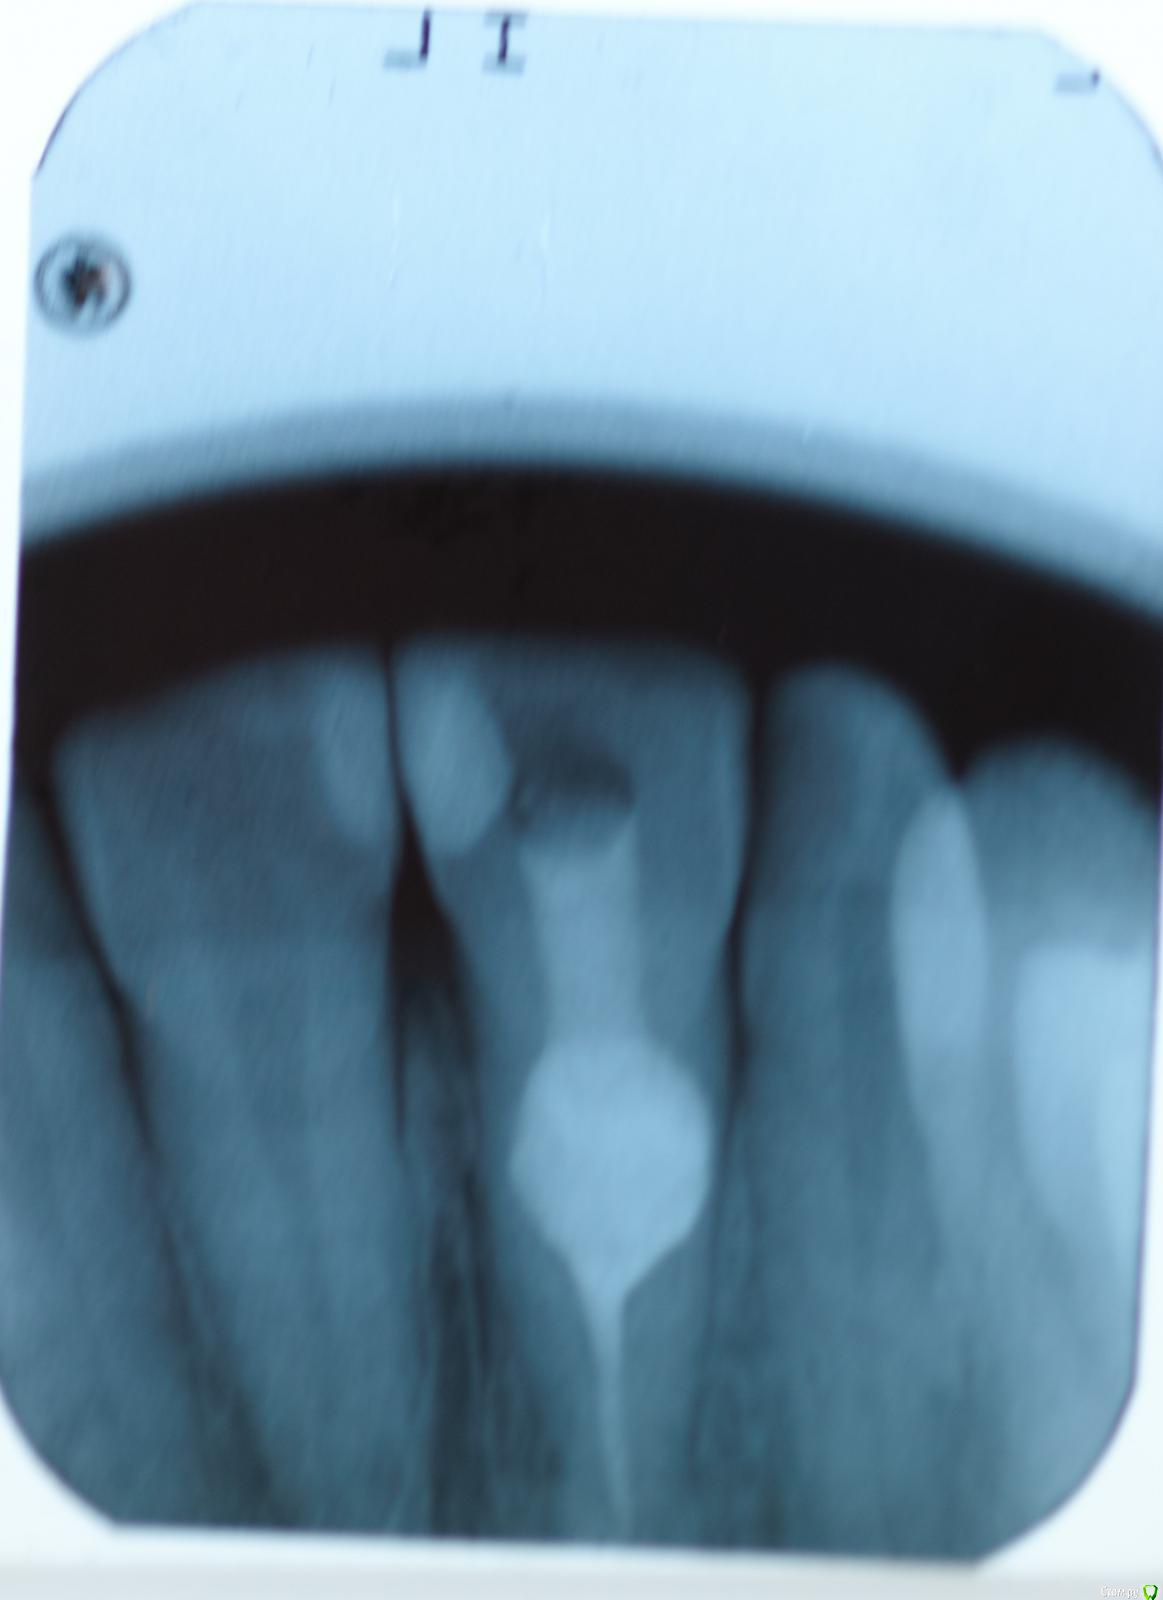

skeettrap Опубликовано 5 апреля, 2016 Автор Поделиться Опубликовано 5 апреля, 2016 (изменено) Латеральная конденсация. В очаге резорбции - МТА. Изменено 5 апреля, 2016 пользователем skeettrap Ссылка на комментарий

skeettrap Опубликовано 7 июня, 2016 Автор Поделиться Опубликовано 7 июня, 2016 (изменено) Наконец пациентка дошла. Пока все нормально и свищ не появлялся больше. Зуб 21. Изменено 7 июня, 2016 пользователем skeettrap 3 Ссылка на комментарий

vse32 Опубликовано 7 июня, 2016 Поделиться Опубликовано 7 июня, 2016 У внутренних резорбций самый предсказуемый прогноз. Главное вычистить всю органику из канала и зоны резорбции. Тогда процесс остановится.Минус, если резорбция перфарирующая. Но и здесь все зависит от площади перфорирования и аккуратности. Самое сложное в таких случаях - запломбировать канал за зоной резорбции.Поздравляю. Ссылка на комментарий